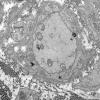

PERIPHERAL NEUROPATHY

6 AXONAL DEMYELINATION (BASIC PROCESS)